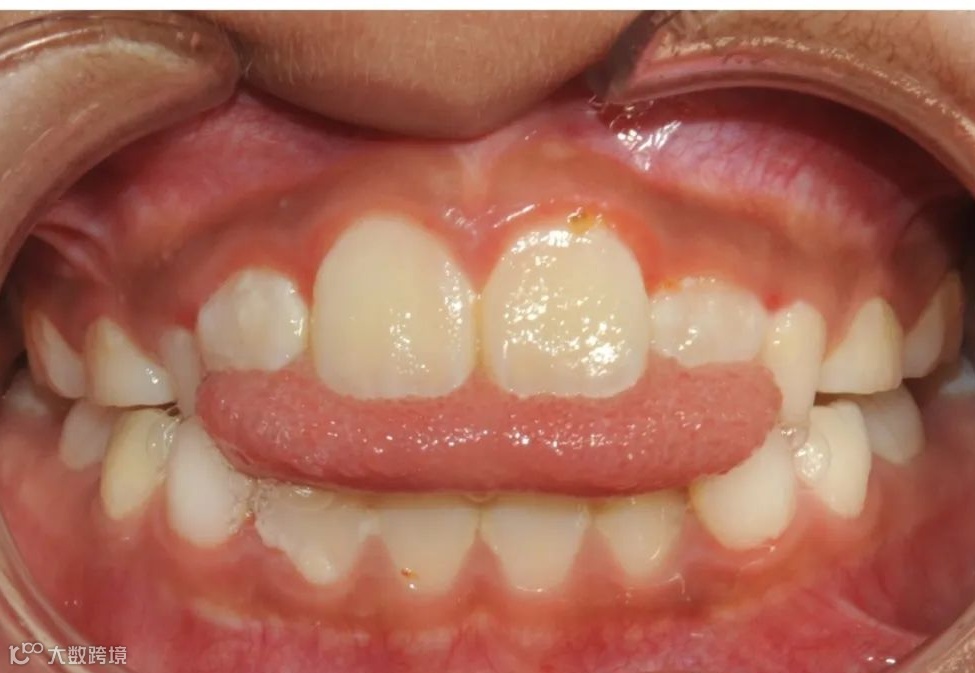

替牙期牙性反𬌗治疗前

替牙期牙性反𬌗治疗后